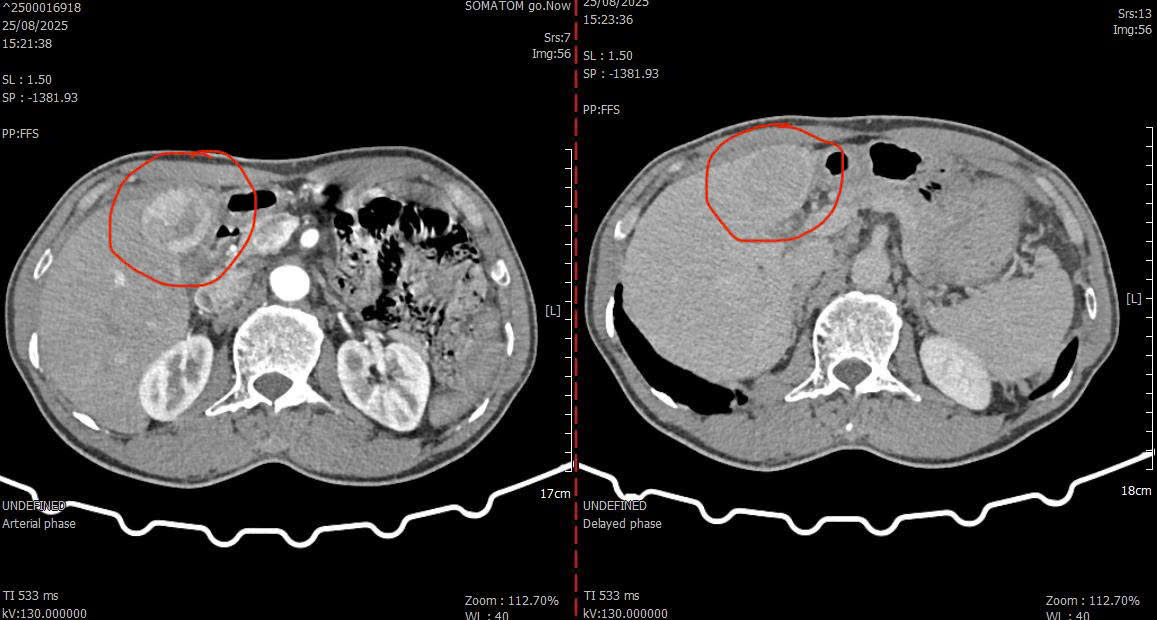

Hình ảnh khối u chụp cắt lớp vi tính trước can thiệp.

Ông T.H.C. (66 tuổi, quê xã Tam Anh, TP. Đà Nẵng) nhập viện vào ngày 28/8 trong tình trạng sức khỏe yếu, nhiều bệnh nền phức tạp gồm: bệnh phổi tắc nghẽn mạn tính (COPD), lao phổi cũ, gout, tiền sử phẫu thuật mở bụng lấy sỏi đường mật phức tạp. Trong quá trình thăm khám, bác sĩ phát hiện khối u gan hạ phân thùy IV-V, kích thước khoảng 5x6 cm, giàu mạch máu – được chẩn đoán là ung thư biểu mô tế bào gan.